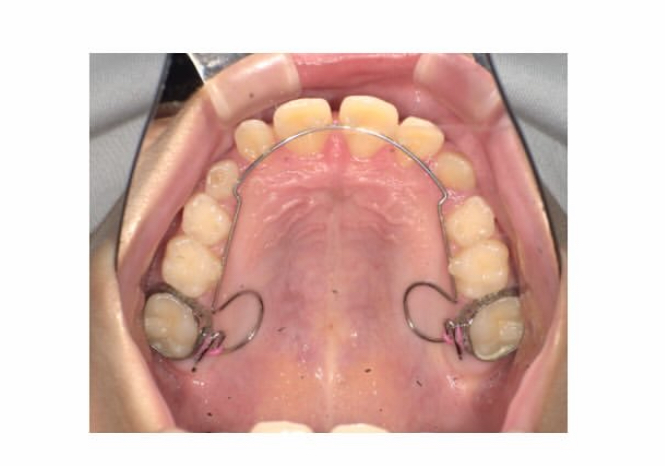

マイオブレース矯正で使う補助装置

上顎に細い針金がつく『BWS』という装置

舌のアクティビティに進んだ段階でBWSという補助装置を3ヶ月ほど使用しました。

この装置が付いている間は舌のアクティビティはやりにくくなりますが

それでも真面目に毎月100%でマウスピースもアクティビティも取り組んでくれていました。